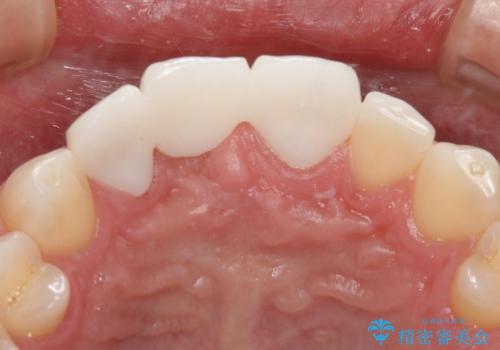

周りの歯との色調に合わせた綺麗なブリッジを入れることができました。